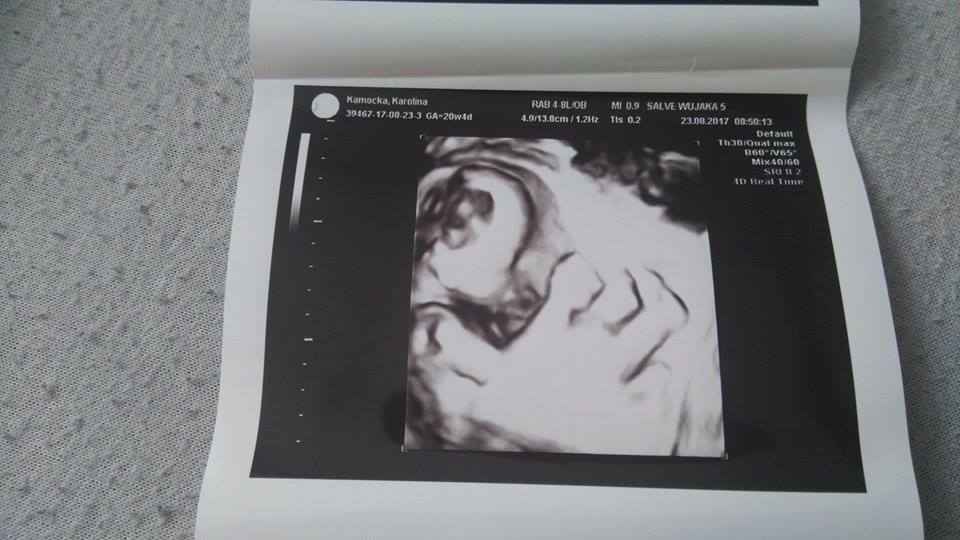

Trafiłam na bardzo fajną Panią doktor, najpierw wszystko pokazała i wytłumaczyła, a potem dopiero robiła pomiary. Mała leży sobie poprzecznie, waży 432g i z USG jest całe 2 dni starsza. Wszystko prawidłowo się rozwija, na swoim miejscu. Dziewczynka potwierdzona, można szaleć z jednorożcami

Łożysko na przedniej ścianie, nic się nie odkleja, szyjka zamknięta, prawie 4 cm.